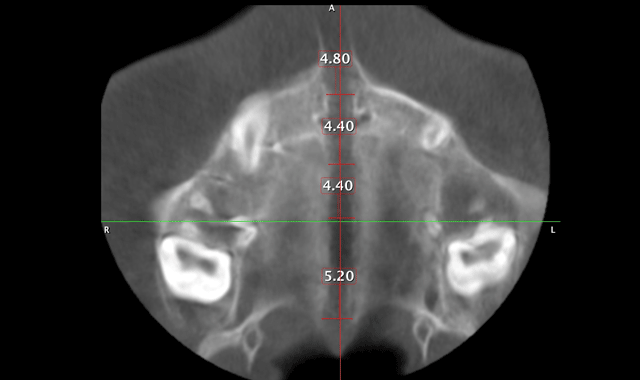

We can now extrapolate a coronal view that allows us to visualize many anatomical structures to formulate a diagnoses and treatment plan. The coronal view with a slice taken through the lingual roots of the maxillary first molars can be used to accurately determine the width of the maxilla and the inclinations of the maxillary molars (Fig. 5). We can then determine the mechanics needed for our patients in this dimension. The mechanics utilized on the patient in Figure 5 were expanded with skeletal fixation of the expander. No bands were attached to the molars.

Therefore, true horizontal expansion was achieved (Figs. 6a, 6b, 6c). These images were taken at the ULD settings on a Planmeca ProMax 3D Mid. Before placing stainless steel wires, many orthodontists will take a progress pan. to evaluate the roots of the teeth as far as proper bracket placements. This is an additional 35 microsieverts when using a traditional 2D panoramic machine. The ULD setting on the Planmeca Pro-Max 3D Mid machine with a limited field of view that only images the teeth is an effective dose of around 9 microsieverts.